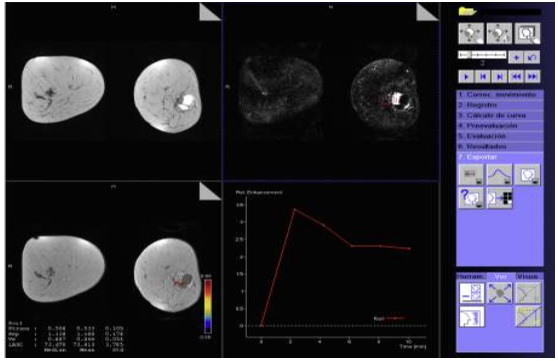

Características en RNM del CMTN

En los resultados de las características en resonancia magnética, se debe tener en cuenta que de las 17 pacientes solo se dispone información de 8 resonancias magnéticas realizadas en centros periféricos. Esto representa el 75% de la muestra, equivalente a 8 casos.

De estos casos se destaca que informan una cantidad de tejido fibroglandular tipo B, aunque no describen el realce parenquimatoso de fondo ni hallazgos asociados.

En lo que respecta a la descripción nodular, se encontró que en el 77,7% de los casos (7 de 8) el nódulo se reportó como redondeado, seguido de la forma ovalada.

Los márgenes del nódulo en 7 casos se describen como circunscritos y solo en 1 caso se reporta como espiculado.

Según lo referido realce interno del nódulo, 5 casos presentaron realce heterogéneo periférico y 3 casos mostraron un realce en forma de anillo.

Finalmente, en la evaluación de la valoración de las curvas cinéticas, se notó que en la fase inicial los 8 casos tenían una fase rápida. En la fase tardía, 6 de los casos presentaban un patrón de wash out, mientras que 2 casos mostraban un tipo de realce en meseta.

Los resultados de resonancia magnética mostraron hallazgos consistentes con la literatura, incluyendo el realce periférico, nódulos heterogéneos y curvas cinéticas tipo 2 y 3. A pesar de la limitada disponibilidad de resonancias magnéticas en centros periféricos, estos hallazgos respaldan la utilidad de esta técnica en la evaluación de tumores mamarios.

Anexo 3. Imágenes CMTN en resonancia magnética